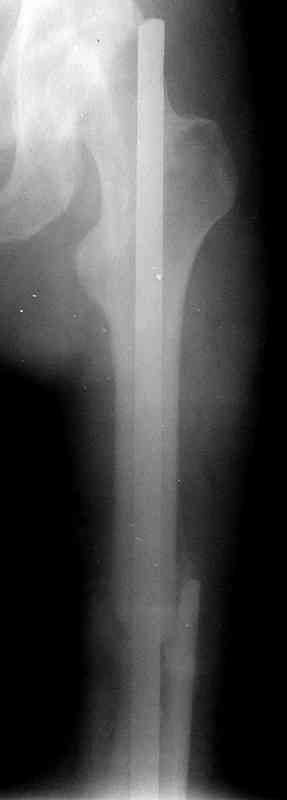

по его наружной поверхности послеоперационный рубец - рана зажила первичным натяжением. При измерении длины бедер обнаружено укорочение левого бедра на 4,5 см. На рентгенограммах этого бедра: ось конечности правильная, отмечается захождение основных костных фрагментов по длине, проксимальный конец штифта выступает слишком медиально и высоко относительно большого вертела, периостальная мозоль незначительна.22.12 - через 6 месяцев после операции, произведенной в ЦРБ, нами по поводу замедленно консолидирующего перелома левой бедренной кости с ее абсолютным укорочением под наркозом произведена операция: удаление штифта, закрытый блокирующий интрамедуллярный остеосинтез перелома левого бедра штифтом без рассверливания (UFN) длиной 40 см, диаметром 10 мм с блокированием только проксимальных отверстий (динамический остеосинтез). Наложен аппарат Илизарова на 4 полукольцах с целью удлинения укороченного бедра. Послеоперационное течение без особенностей. Ежедневно осуществляли дистракцию отломков на 1 мм. Через 3 недели после операции больной выпи-сан на амбулаторное лечение с продолжением дистракции отломков. В течение 1,5

месяцев дистракции укорочение левого бедра удалось полностью устранить. 22.02.00, т.е. через 2 месяца после повторного остеосинтеза, больному произведено дистальное блокирование штифта двумя винтами и демонтирован аппарат Илизарова. В течение 2 недель после операции больной ходил с помощью костылей, потом 2 недели с тростью. Опороспособность и функция оперированной конечности полностью восстановились через 4 недели после операции.